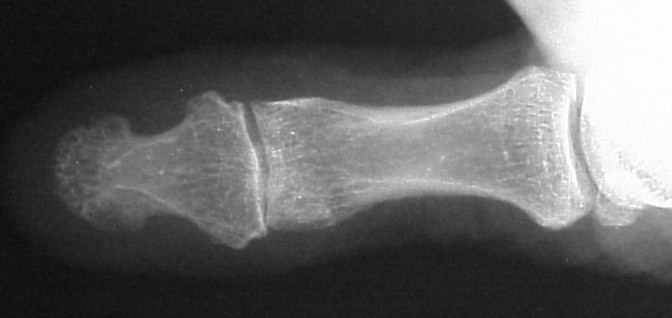

Plain films showed resorption of the distal two thirds of the distal phalanx:

Comparison views of the opposite side: